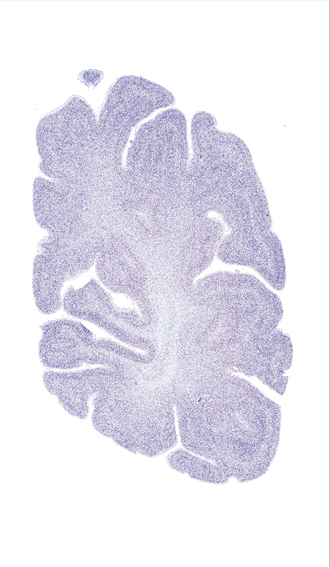

Hi-Resolution Sections · Cells (Nissl Staining) · Virtual Microscopy

Frontal sections (Nissl) from the Atlas Brain:

Slice ID:

r4-1024

Plate NR:

60

Position:

64,5 mm